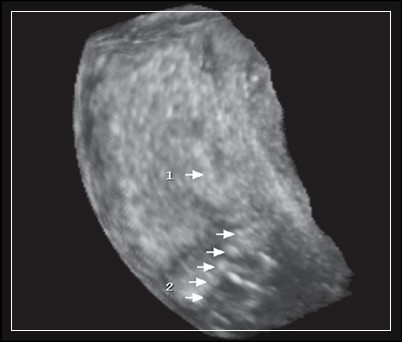

Субинволюция матки на УЗИ

• Ультразвуковые исследования. Для диагностики осложнения применяют трансабдоминальное и трансвагинальное УЗИ органов малого таза, трехмерную эхографию. Определяется высокое стояние дна матки, не соответствующее послеродовому сроку, утолщение ее стенок. Эхография позволяет точно определить наличие инородных тел и остатков последа в маточной полости.